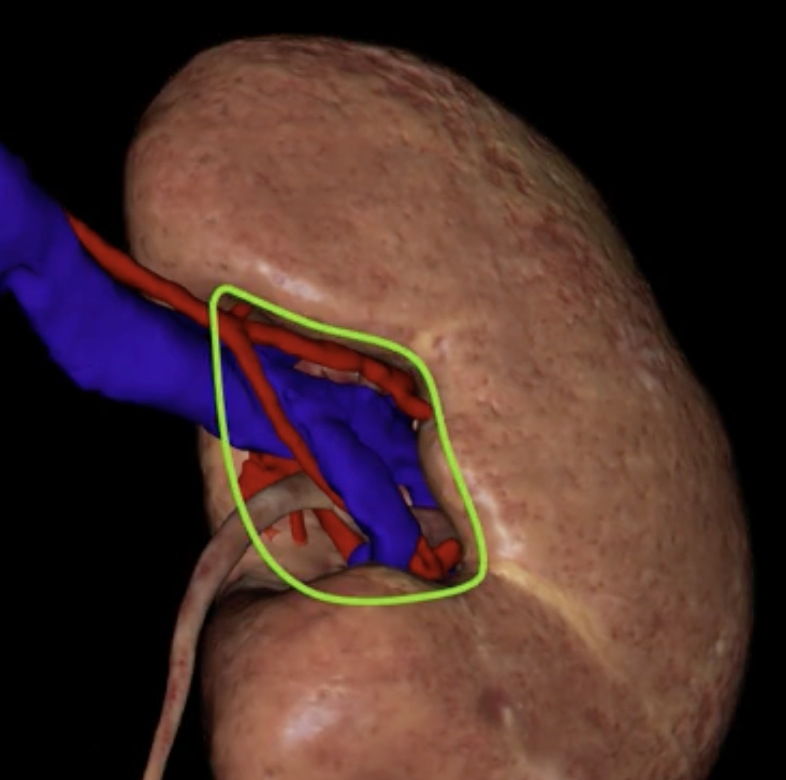

hilum

green

green: renal hilum

yellow: ureter

red: abdominal aorta

green yellow and red